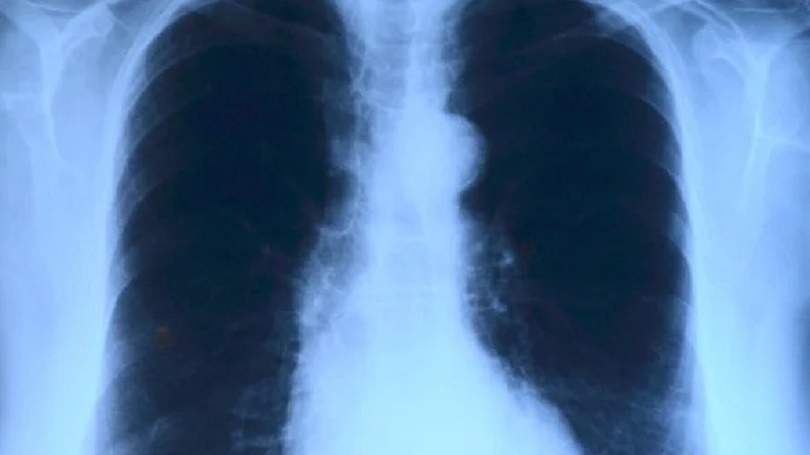

Nowotwory płuc dotyczą zarówno kobiet jak i mężczyzn. Mimo coraz nowocześniejszych metod leczenia nadal zbierają ponure żniwo. Teraz nadarza się okazja by bezpłatnie się przebadać i wykluczyć tę bardzo poważną, nieraz śmiertelną chorobę.

Nowotwory płuc stanowią bardzo istotny temat, na co wskazują statystyki publikowane przez Światową Organizację Zdrowia.

Według niej rak płuca jest najczęściej występującym nowotworem na świecie. Około 85-90% zgonów z jego powodu jest ściśle związanych z paleniem tytoniu. Szczególnie narażeni są palacze: